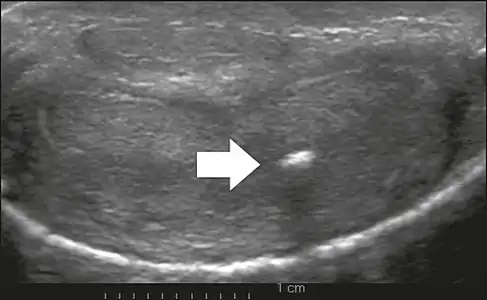

On penile ultrasonography, the typical appearance is hyperechoic focal thickening of the tunica albuginea. Due to associated calcifications, the imaging of patients with Peyronie's disease shows acoustic shadowing, as illustrated in figures below. Less common findings, attributed to earlier stages of the disease (still mild fibrosis), are hypoechoic lesions with focal thickening of the paracavernous tissues, echoic focal thickening of the tunica without posterior acoustic shadowing, retractile isoechoic lesions with posterior attenuation of the beam, and focal loss of the continuity of the tunica albuginea.

- Transverse ultrasound of the penis, in a ventral view, in the middle portion of the penis. Note the echoic image with posterior acoustic shadowing, corresponding to calcification (arrow), in the left corpus cavernosum.[13]